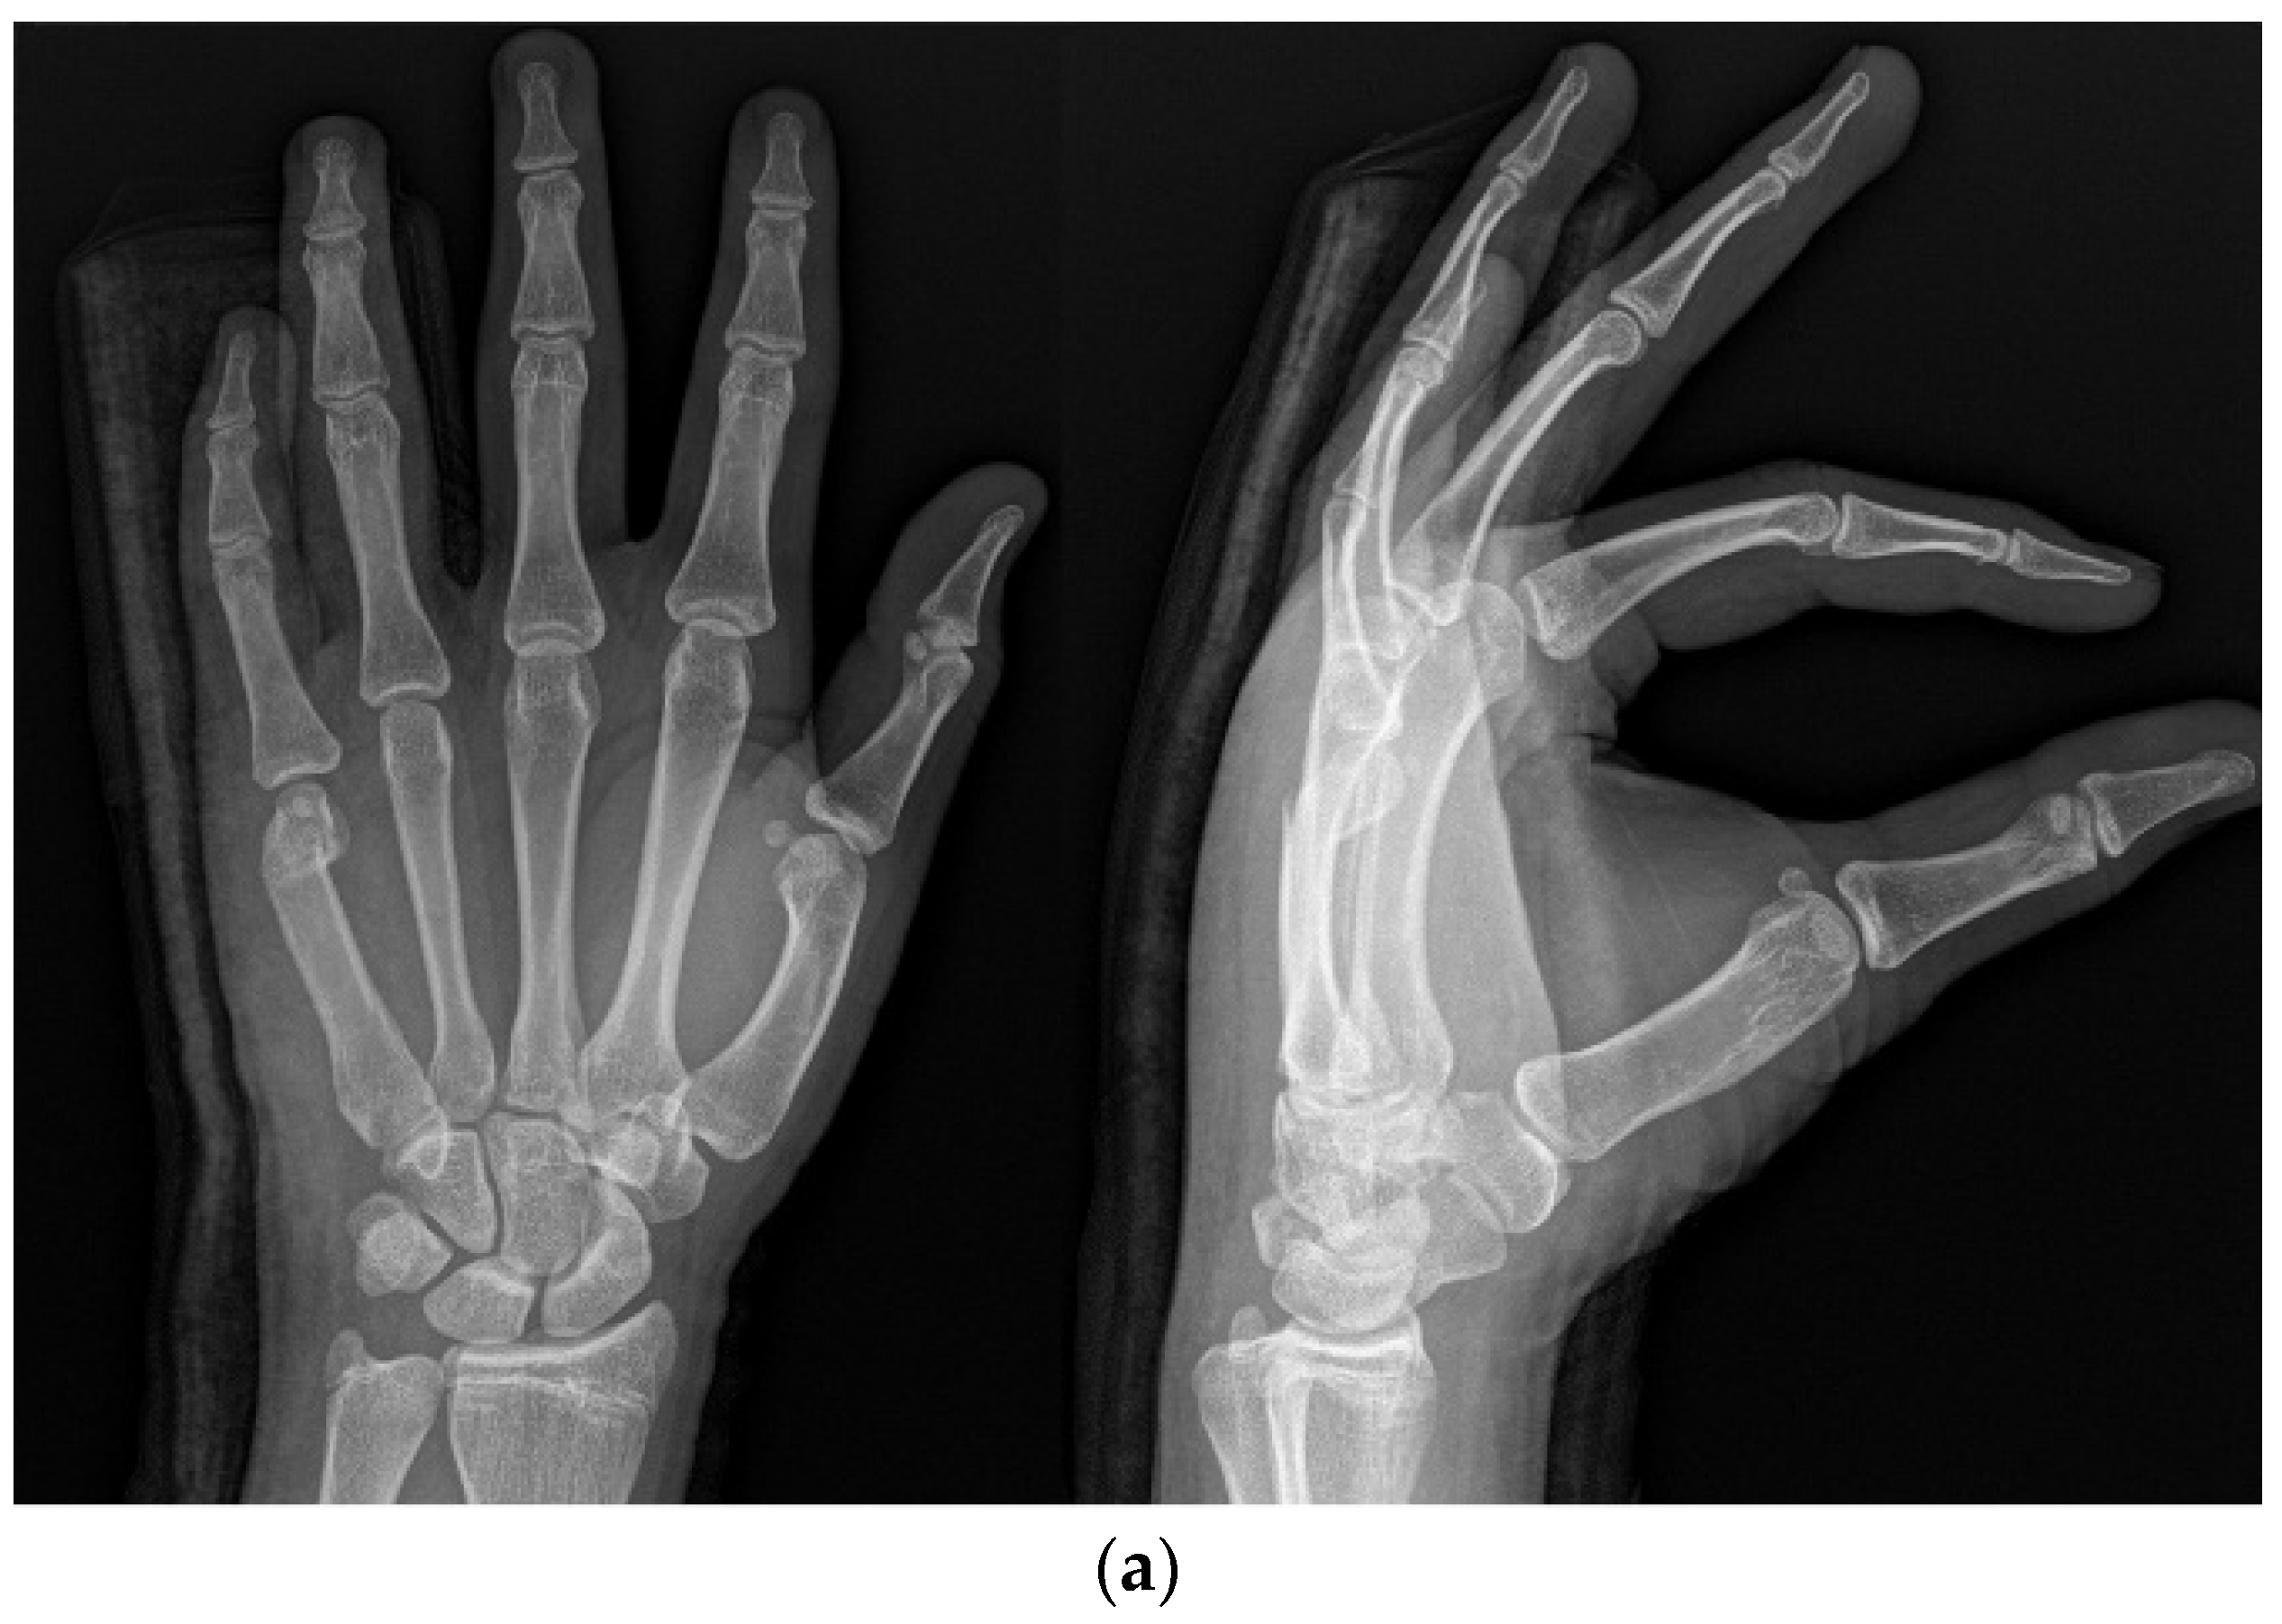

The IP method involved the insertion of an intramedullary nail in the anterograde direction. The entry point was selected at the base of the ulnar dorsal border of the metacarpal using a needle under imaging guidance. A small hole was made with a drill, into which the operator inserted the nail. The fracture was reduced via maneuver, and the nail passed across the fracture part (Figure 2a,b).

Figure 2.

(a) Radiograph of a 16-year-old male patient with displaced little-finger metacarpal neck fracture. (b) Radiograph of a 16-year-old male patient who underwent the IP method using one intramedullary nail in the anterograde direction.